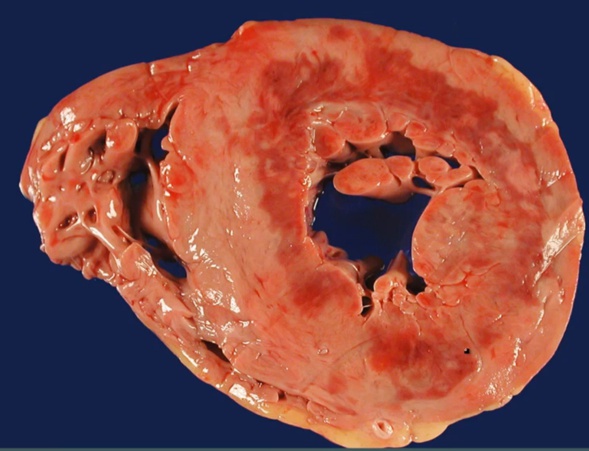

Progression and Complications

_..

Overview:

1st thing: coagulative necrosis: removed nucleus from cells

2nd: acute inflammation with neutrophils/macrophages

3rd: healing, granulation, then conversion to scars

< 4 hours:

congestive heart failure: blood back up and can’t pump

arrythmia from damaged conduction

1-7 days:

WBC gives yellow pallor gross color

complication depends on whether neutrophil or macrophages

neutrophil: transmural inflammation, exudate leak to pericardium, pericarditis. Only with transmural inflammation

macrophage: eat up all dead debris, wall = weakest, rupture

1-3 weeks:

granulation: blood vessels, red border from outside, from normal tissues

months:

scar: not as strong as myocardium, not good movement, stasis, aneurysm/thrombus

1 day, 1 week, 1 month

1st day: coagulative necrosis

after 1st day: inflammation up to 1 week, neutrophil then macrophage

after 1 week: granulation

1 month: scar

subendo, mottled color

coagulation necrosis

inflammation

pericarditis

rupture

papillary muscle

scar

collagen, CT, type 1

aneurysm